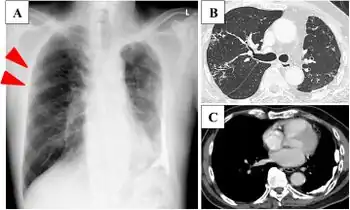

a) Chest X-ray image shows a reticular shadow in right upper lung b,c) high-resolution CT showed centrilobular micronodules in right upper lobe